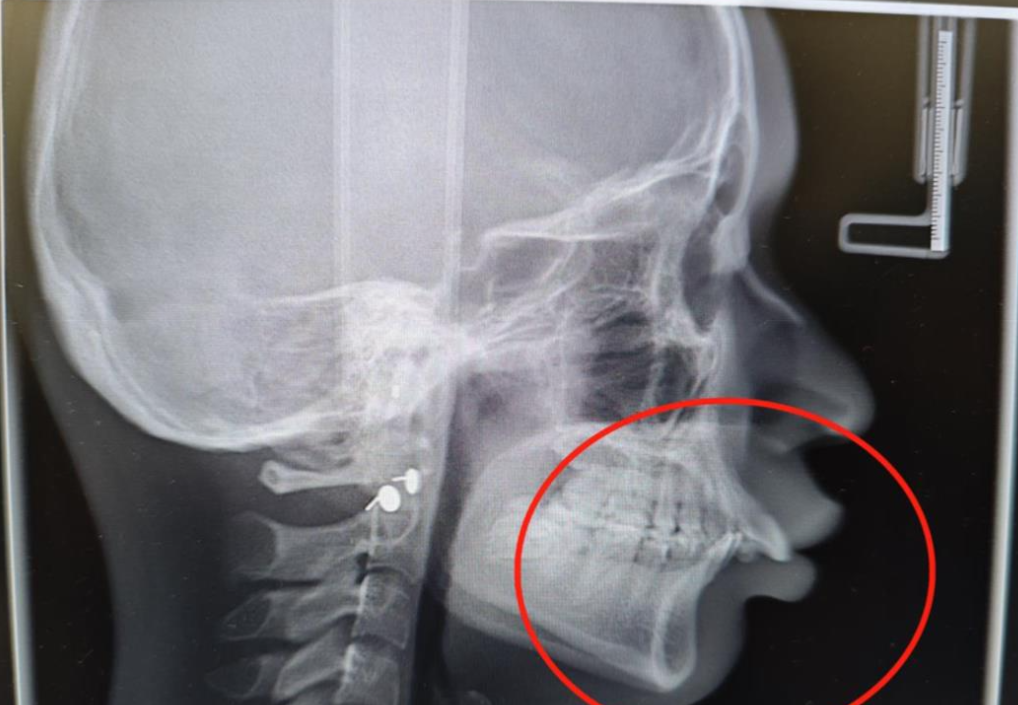

近3年时间里,医生根据牙齿移动的情况,平均每7~10天3D打印一套牙套,到现在已有60多副,整个过程更安全、更精准。最新拍片可见,小宁有了明显变化,上颌骨、牙齿成功回缩,她的脸上又有了明媚笑容。